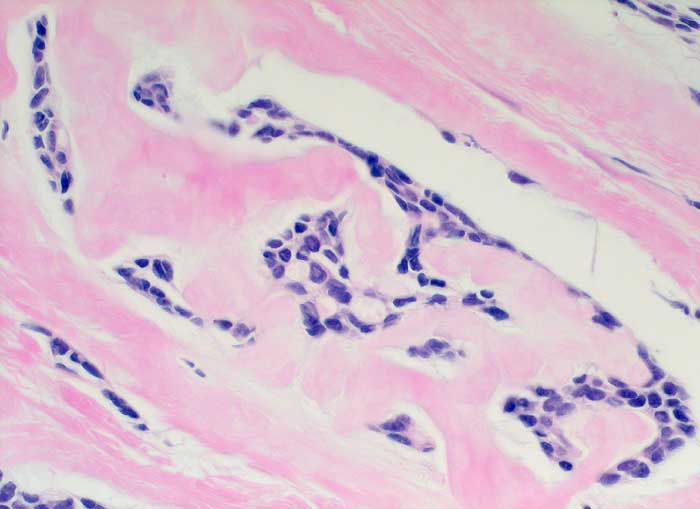

Adenoidzystisches Karzinom

Dichtes amyloidartiges Stroma umschliesst residuelle zylindromatöse Knoten.

Adenoidzystische Karzinome kommen vor allem im Bereich der Speicheldrüsen vor, treten aber auch in anderen Organen auf. Sie machen weniger als 0.1% - 0.2% der Mammakarzinome aus.

Histologie

400